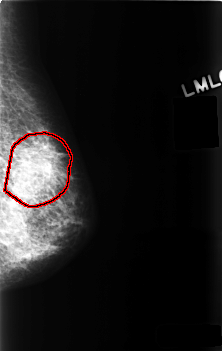

C_0481_1.LEFT_MLO

LEFT_MLO LINES 4560 PIXELS_PER_LINE 2880 BITS_PER_PIXEL 12 RESOLUTION 50 OVERLAY

FILE: C_0481_1.LEFT_MLO.OVERLAY

TOTAL_ABNORMALITIES 1

ABNORMALITY 1

LESION_TYPE MASS SHAPE ARCHITECTURAL_DISTORTION MARGINS ILL_DEFINED

ASSESSMENT 5

SUBTLETY 4

PATHOLOGY MALIGNANT

TOTAL_OUTLINES 1

BOUNDARY